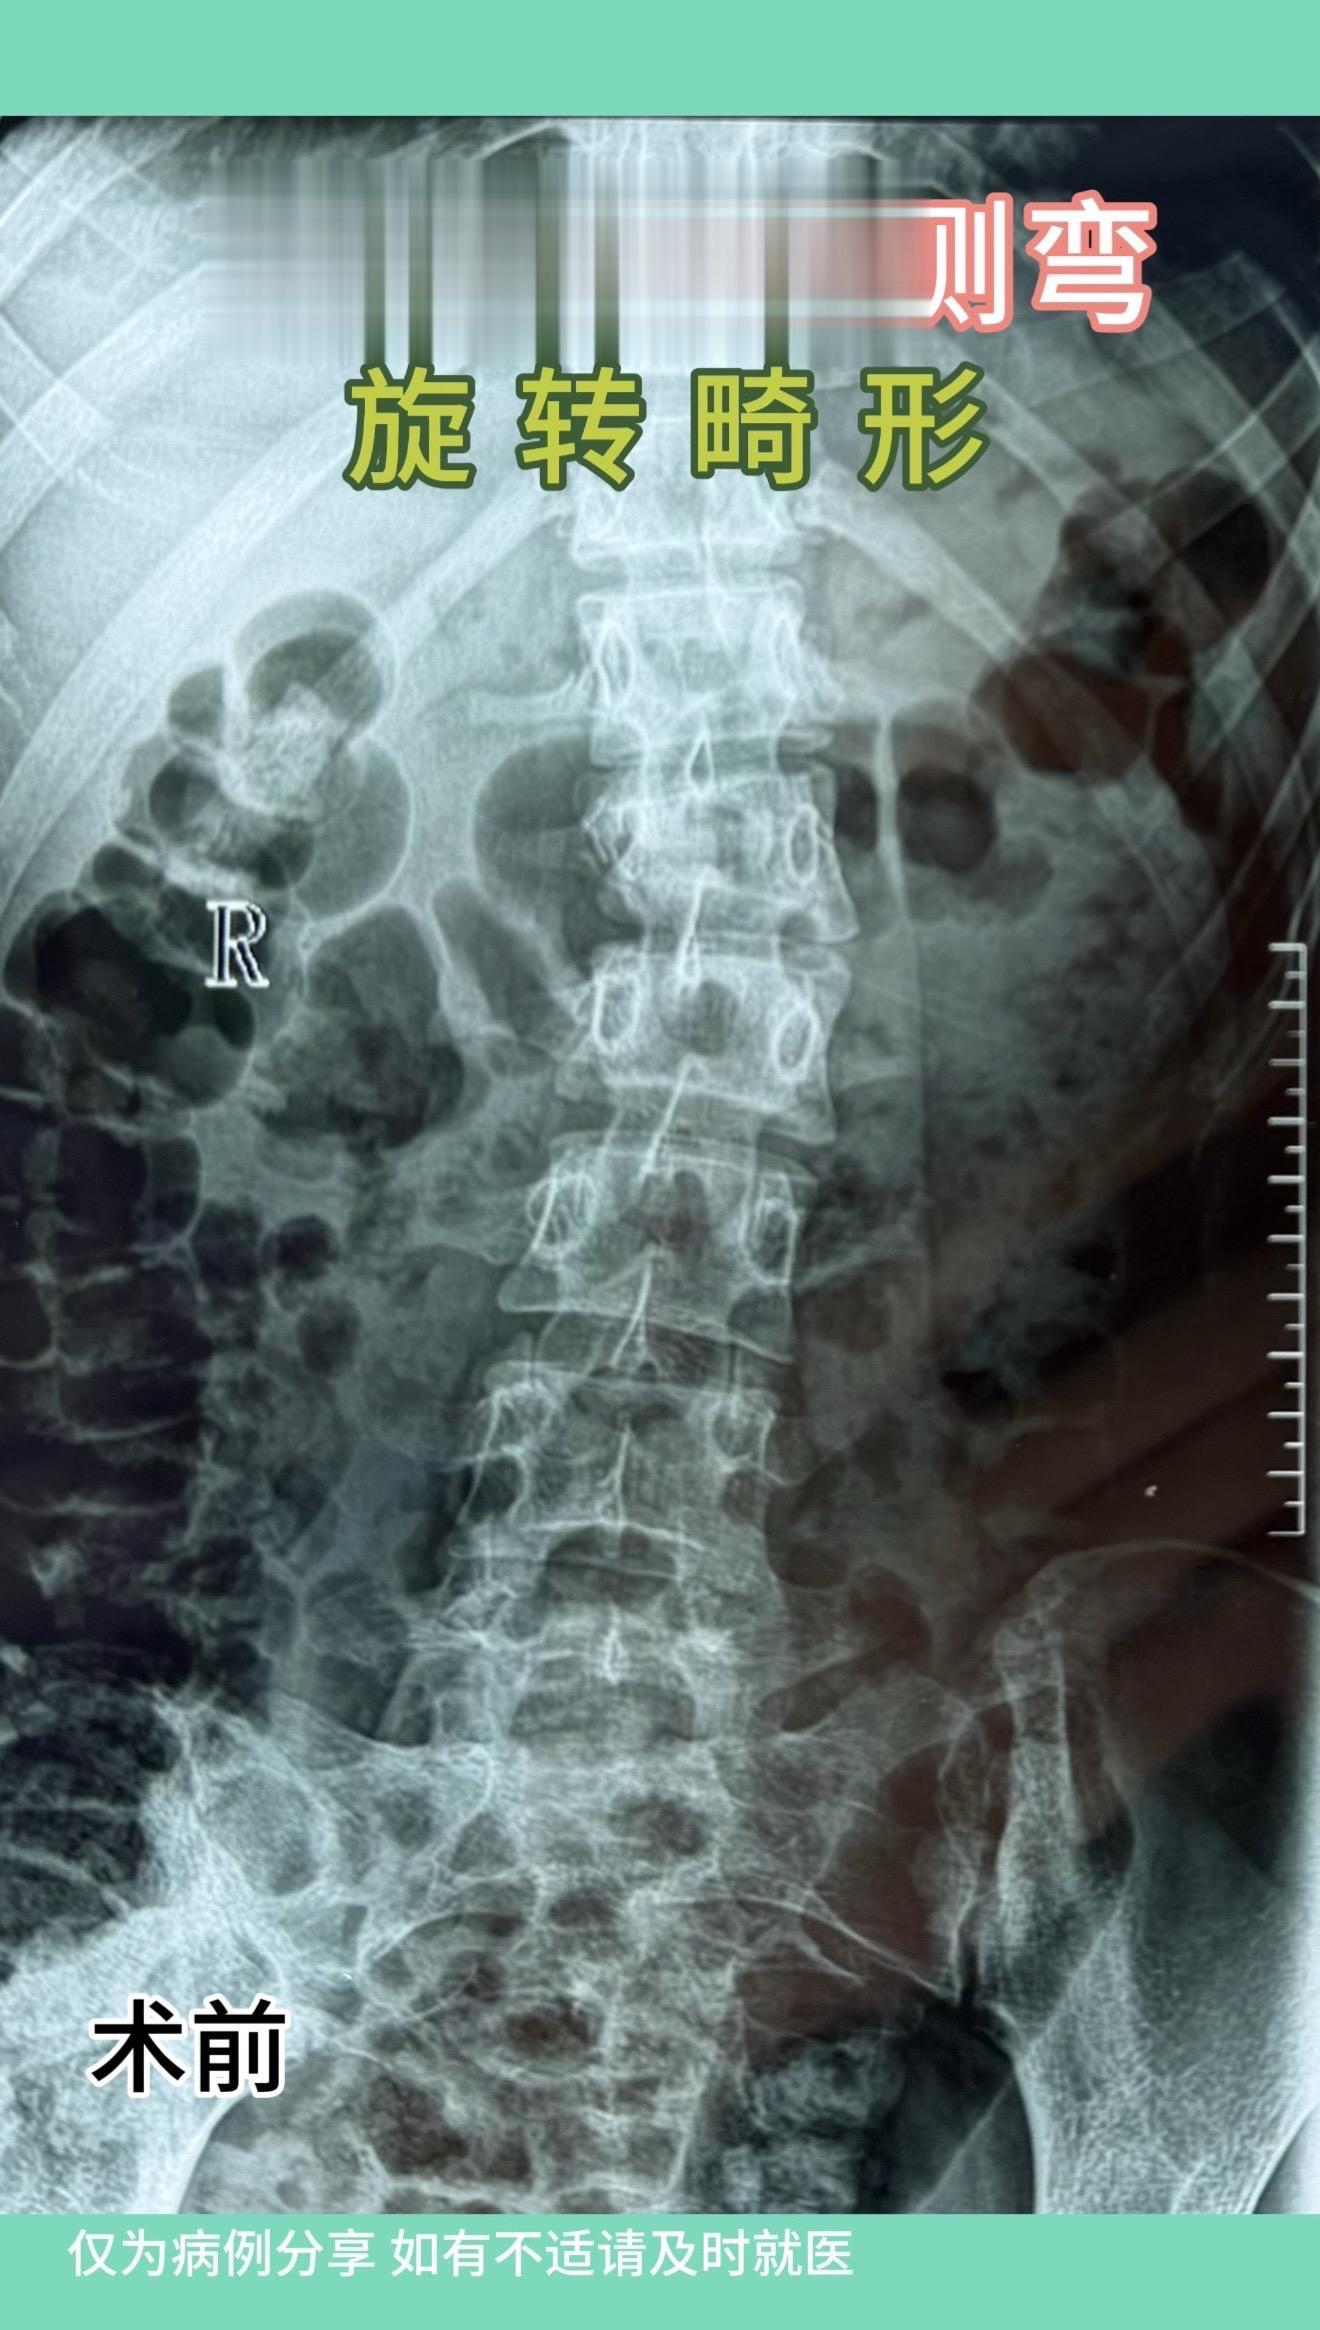

17岁女孩,车祸后腰1骨折伴侧弯,旋转畸形。术后畸形恢复好。